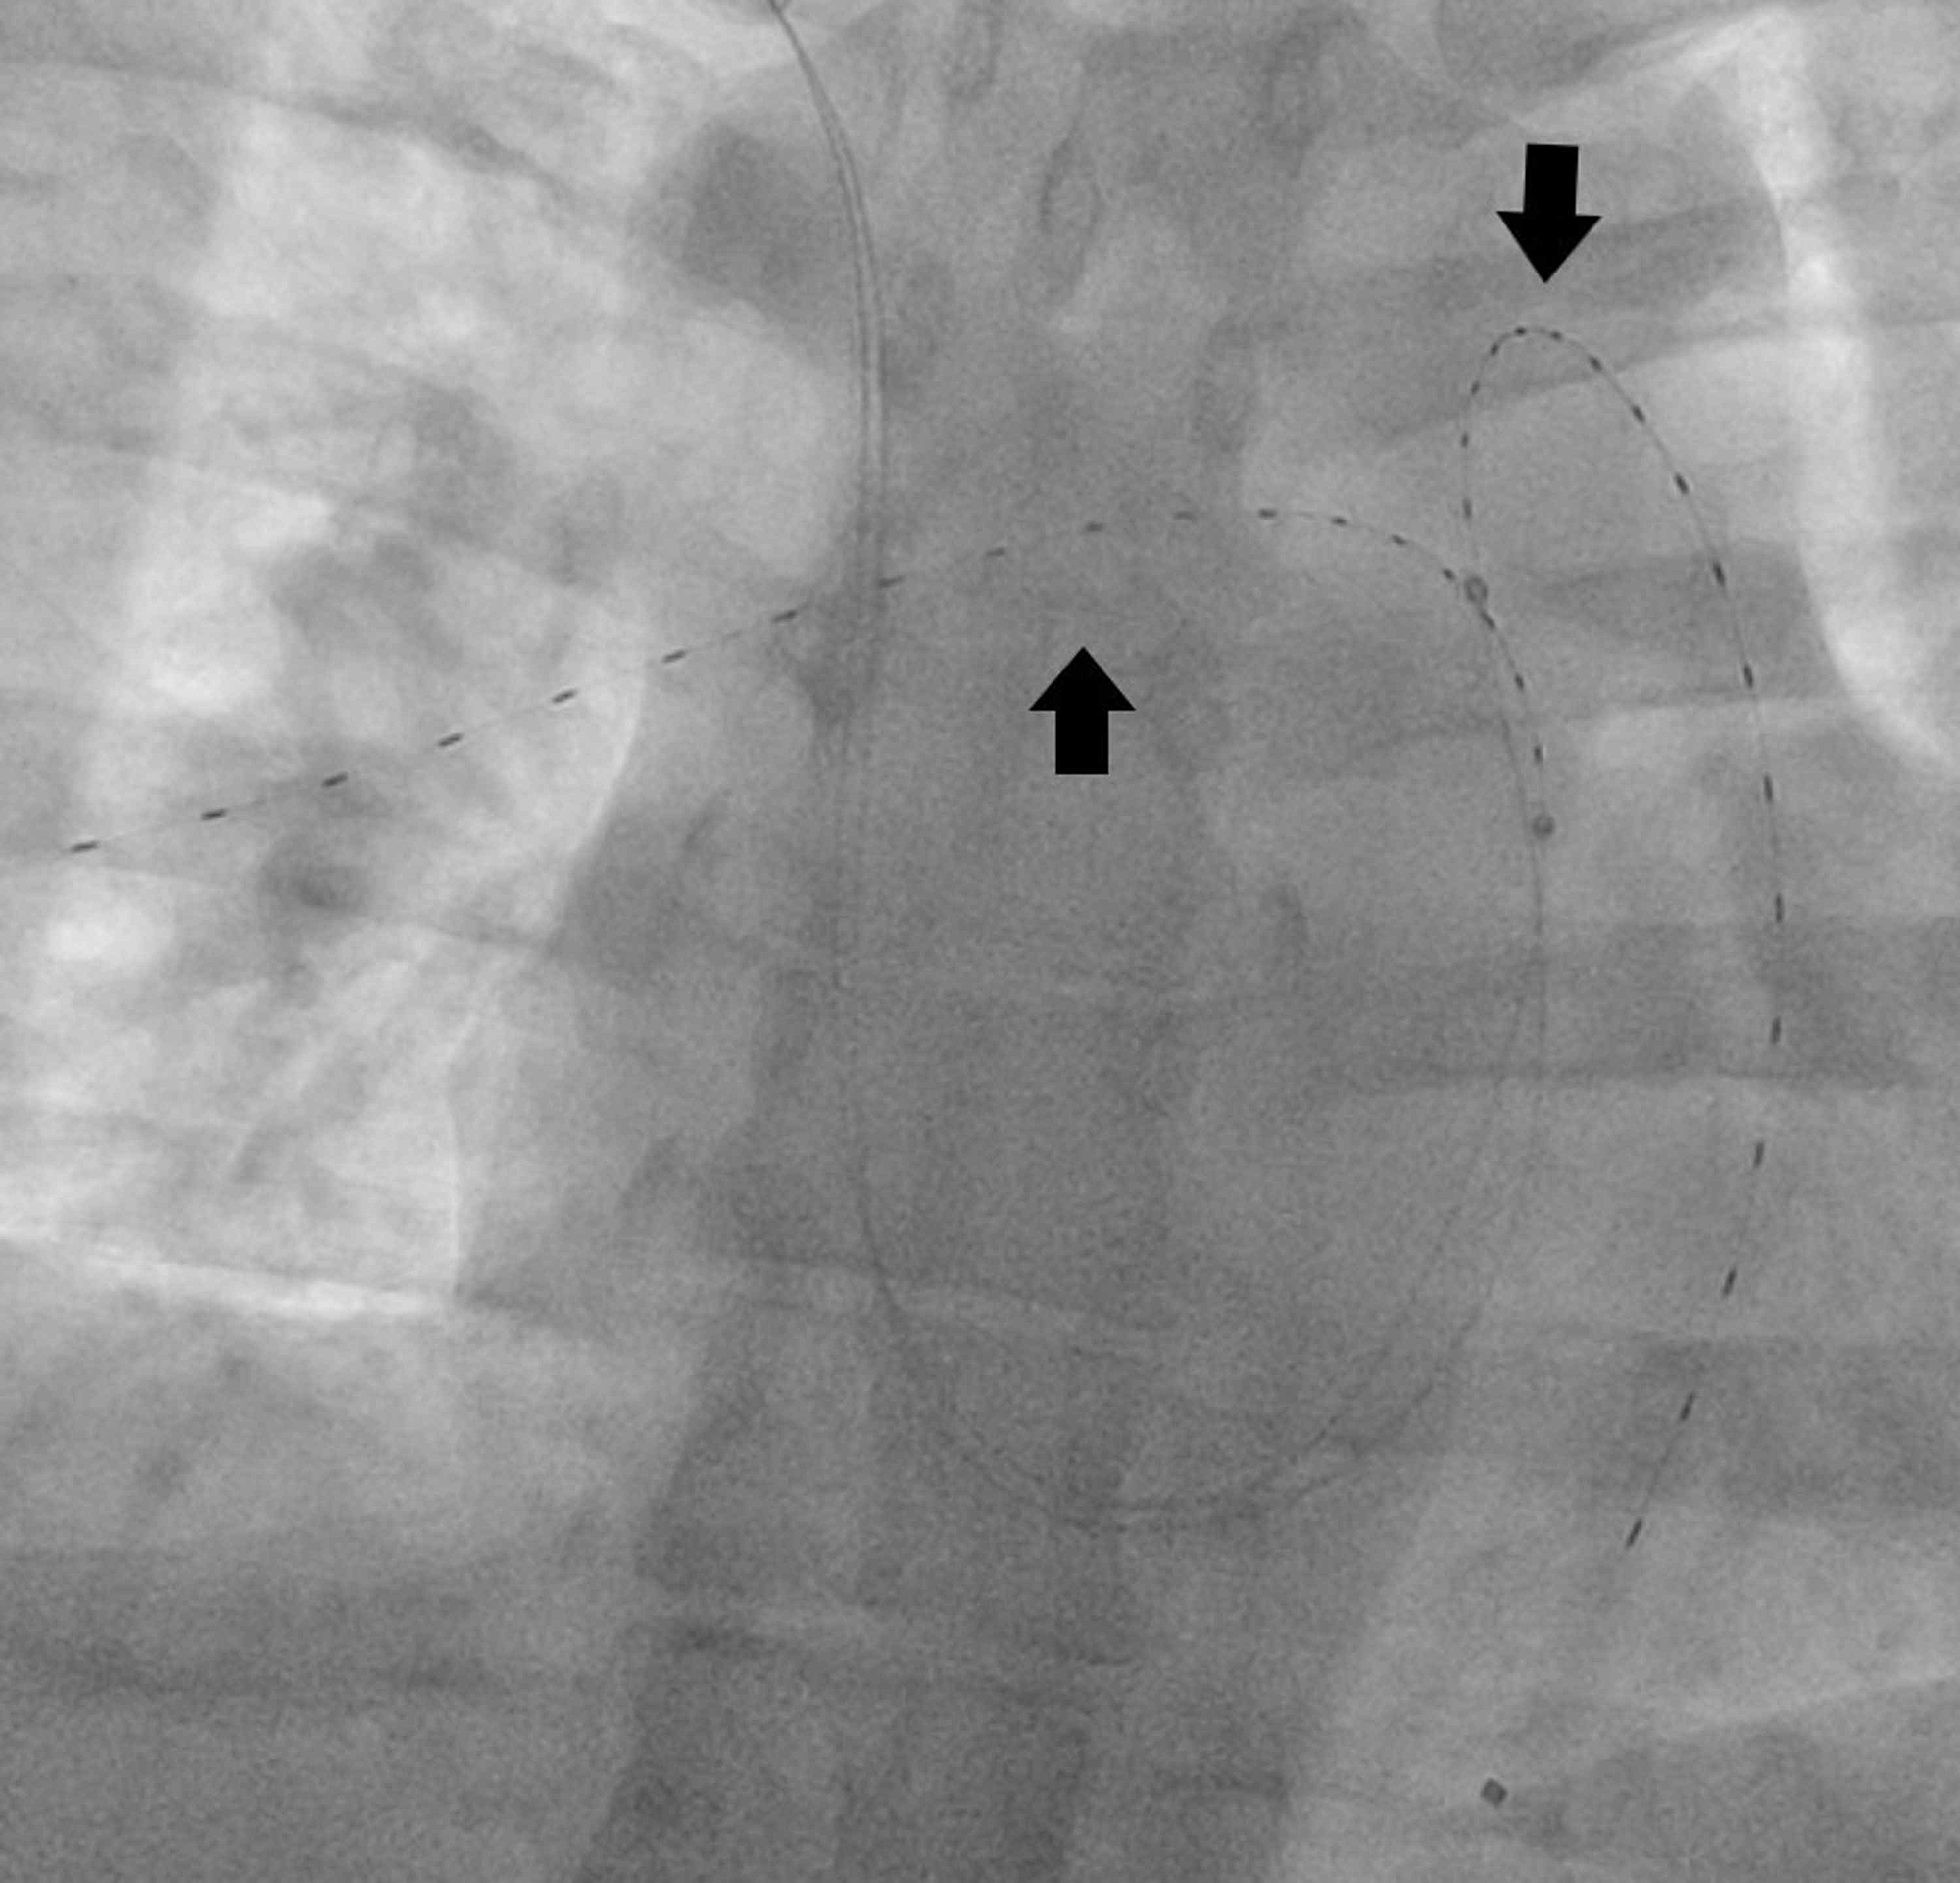

Evaluation of the Benefit of Extended CatheterDirected Thrombolysis

CatheterDirected Thrombolysis With the Bashir Catheter Directed Thrombolysis Pulmonary Embolism Web a recently published prospective registry of 101 patients with acute pe (perfect [pulmonary embolism response to fragmentation,. Web pulmonary embolism (pe) is an increasingly common cause of cardiovascular death. 1 rapid implementation of advanced. Catheter Directed Thrombolysis Pulmonary Embolism.

Cureus UltrasoundFacilitated CatheterDirected Thrombolysis via Dual Catheter Directed Thrombolysis Pulmonary Embolism Web pulmonary embolism (pe) is an increasingly common cause of cardiovascular death. 1 rapid implementation of advanced. Web a recently published prospective registry of 101 patients with acute pe (perfect [pulmonary embolism response to fragmentation,. Catheter Directed Thrombolysis Pulmonary Embolism.